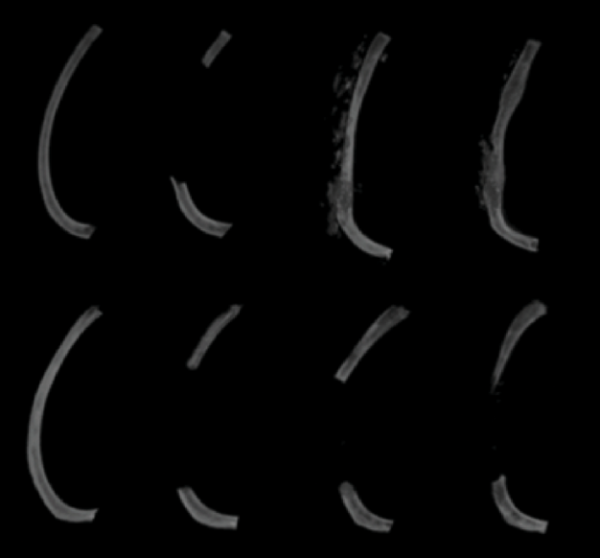

To do so, they began by removing a bit of bone from the ribs of mice younger than two months of age or older than ten months. Just like in humans, the missing piece of rib regenerated in the younger mice but not the older mice, which filled the gap in the bone with scar tissue and fat instead. Part of the reason for this difference was that, in the younger mice, genes involved in the production of bone and cartilage — a crucial secondary component of strong bones — were more active in the damaged area of bone compared to in the older mice.

As shown in this representative image from the study, immature mice (top row) regenerated their missing section of rib bone over time while mature mice (bottom row) did not, even 60 days after the section was removed (far-right column).